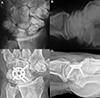

![]() |

Figure 7 Clinical case of 4-Corner Fusion. A and B. Preoperative wrist X-rays of SNAC stage II (AP and Lateral views). C and D. Postoperative wrist X-rays (AP and Lateral views) after 17 years. Source: Dr. Emmanouil Apergis. |